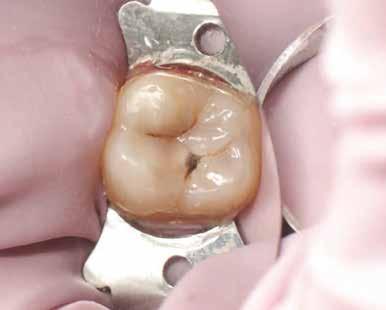

A szerző helyi érzéstelenítés után a fogat latexmentes kofferdámmal izolálta; a gumit befordította, és közben fogselyem segítségével interproximálisan visszahúzta (11. ábra)

Nagyítás alatt (operációs mikroszkóp) a régi restaurációt körte alakú gyémántfúróval távolította el, 1,5-es sebességfokozatú elektromos kézidarabbal kb. 45 000/ perc fordulatszámon vízhűtés mellett, így a mesiális oldalon feltárta a szuvasodást. A szerző az elektromos kézidarabot részesíti előnyben a nagy nyomaték és a kisebb, alacsonyabb sebességnél előforduló torpanási hajlam miatt. A szomszédos premoláris fogat ék (Triodent) segítségével védte az iatrogén sérülésektől (12. ábra). A szomszédos fog iatrogén sérülése jól dokumentált komplikációja a II. osztályú üreg dobozpreparációjának [18].

A cariest lépésről-lépésre távolította el, caries detektáló festék és a Peripheral-Seal koncepció [15] alkalmazásával, amely lehetővé teszi a magas kötőerejű, cariesmentes zománc- és dentinzóna kialakítását a kavitás peremén, miközben a mélyebben lévő, caries által érintett dentin megmarad remineralizáció céljából [16]. A preparáció szélét alumínium-oxid abrázióval kezelte a biofilm és az aprizmatikus zománc eltávolításának céljából, ezzel javítva a kötőerőt [17]; majd karbidfúrókkal elsimította, hogy eltávolítsa a mikroszkopikus szinten törött zománcprizmákat, így csökkentve a „Enamel Peel”-ből eredő fehér vonalak kialakulásának kockázatát (13. ábra) [18].

A fogat 37%-os foszforsavval kondícionálta, majd egy 4. generációs dentin bondot (Optibond FL, Kerr) alkalmazott. A II. osztályú dobozt először centripetálisan zárta [19], folyékony és melegített kompozit kombinációjával, szekciós matrica segítségével.